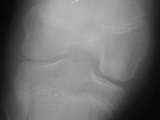

DJD Knee

DJD Knee